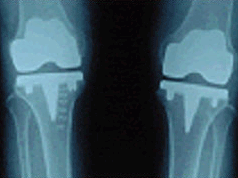

나이가 들어가면서 관절이 닳아 없어지는 퇴행성관절염은 특히 무릎 관절에 많아 인공관절 치환술을 받게 되는 가장 흔한 원인입니다. 휴식과 물리치료, 약물요법 등에 효과가 없고 염증 및 통증이 심할 경우 통증을 없애고 관절의 운동 및 안정성을 회복시키는 목적으로 시행합니다.

류마티스성 관절염이 악화되면 심한 관절 파괴 및 변형을 초래하면서 통증이 조절되지 않습니다. 이런 경우에도 인공관절 대치술을 받아야 합니다. 부위별로 보면 무릎 관절의 류마티스성 관절염으로 인공관절 치환술을 받는 경우가 가장 많고 엉덩이 관절에도 자주 있으며 손가락 관절을 수술하는 경우도 있습니다.

무릎 관절에서 인공 관절 치환술을 받게 되는 흔한 원인 중의 하나로서 무릎 관절을 이루는 대퇴골, 경골 및 슬개골의 골절 후 제대로 붙지 못한 경우 관절염을 초래하여 심한 통증 및 운동 장애를 일으켜 수술이 필요하게 됩니다.